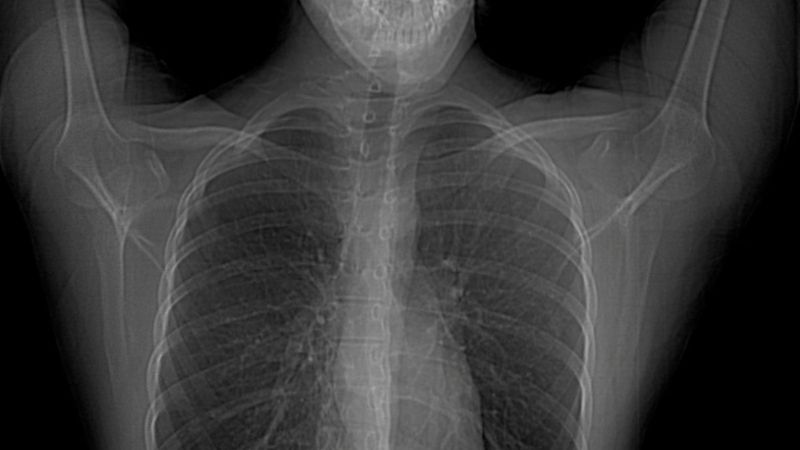

Hastanın vücut yapısı simetrik değildir. Yani vücudun bir yarısıyla diğer yarısı arasında görüntü ve yapı farklılıkları vardır. Özellikle göğüs bölgesinde bulunan yapılarda anormallikler bulunmaktadır. Kişide meme ve meme başı yokluğu da beraberinde görülebilmektedir.

Hastaların göğüs kası olmadığı için bakıldığında simetrik bir görünüm bulunmamaktadır. Estetik bir görüntü olmaması nedeniyle fark edilirler.

Göğüste içbükey bir görünüm vardır. Yine aynı tarafta meme ve meme ucu yokluğu da beraberinde olabilmektedir. Göğüs kaslarına ek olarak kişinin sırt ve kaburgalarında bulunan kasların yokluğu veya burada bulunan kasların liflerinde eksiklik olabilmektedir.